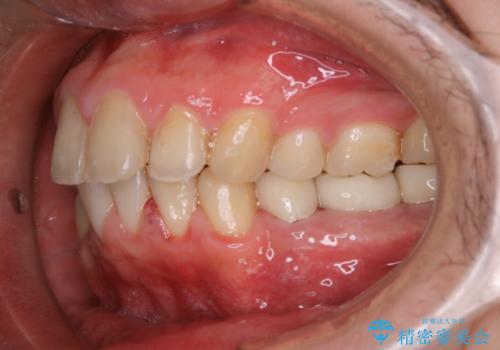

インビザライン矯正治療のスキャニング前のPMTC

- インビザラインでのスキャニング前にPMTCを希望されました。PMTC60分コースを行いました。

矯正治療前には、PMTCで歯石や汚れを取り除き、健康的な歯肉の状態にすることが大切です。PMTCでは、がたつきになどより、ご自身では取り切ることのできない細かい部分などに付着した汚れなども、専門的な機械や材料を使用してクリーニングを行います。